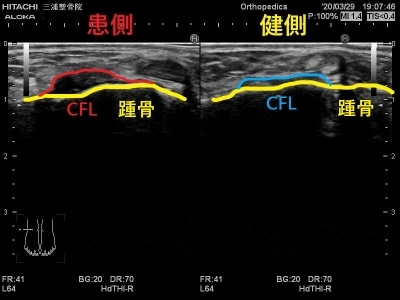

エコーではこのように写ります。

患側では大きく腫れて

正常な靭帯線維が見えないため

二分靭帯が断裂しています。